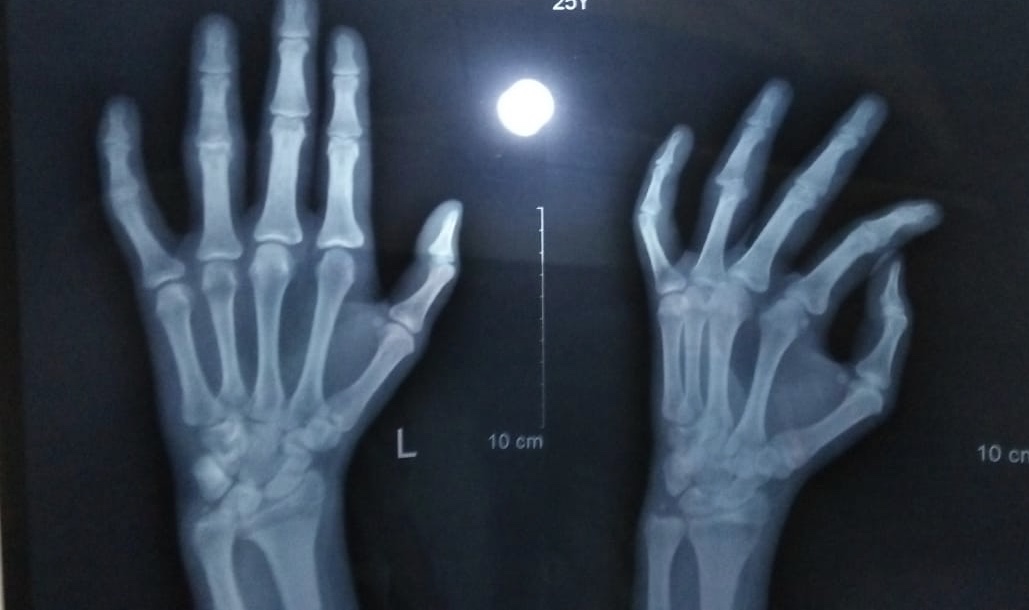

2 months before my brother got an accident hw got injuries on wrist and little finger which was settled down by doctors and put plaster on his lower arm ... aftr a month after removal of plaster X ray exposed his ring finger’s proximal interphlangeal joint dislocation doctors tried it to reposition manually but it could not because of stiffness splint was recommended for a month after a month the condition was same .... i want to ask that is this a case of orthopeadic surgeon or plastic surgery .... and what will be the possible treatment for this condition .... we have to move towards surgical treatment for this issue...? X ray file has been uploaded also